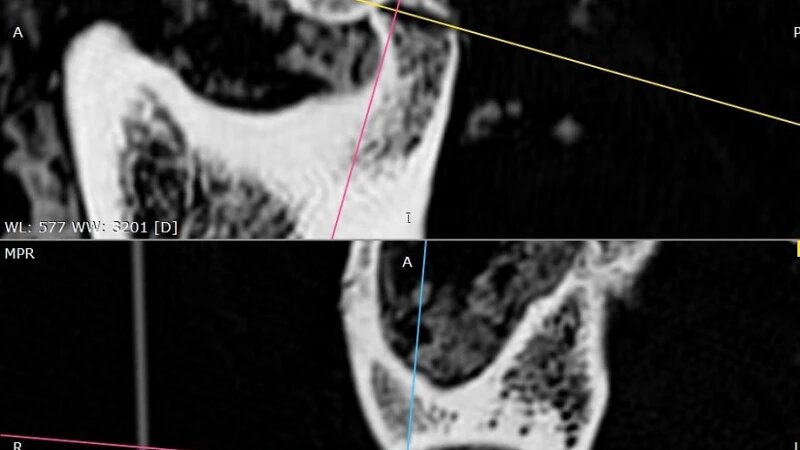

Фото черепа тела женщины возрастом 2,5 тыс. лет. Елена Панфило, пресс-служба НГУ

Как показала компьютерная томография, еще при жизни женщина получила серьезную травму головы, из-за которой разрушился правый височно-нижнечелюстной сустав. Но врачи вернули пациентке способность разговаривать и принимать пищу с помощью операции.

Процедура прошла успешно, после нее древняя жительница Алтая прожила еще значительное время. Это открытие позволило сделать вывод, что уже в то время медицина была достаточно развитой, и люди могли справляться со сложнейшими патологиями.

Кроме того, более ранние исследования показали: врачи еще 2,5 тыс. лет назад умели делать прижизненную трепанацию черепа.